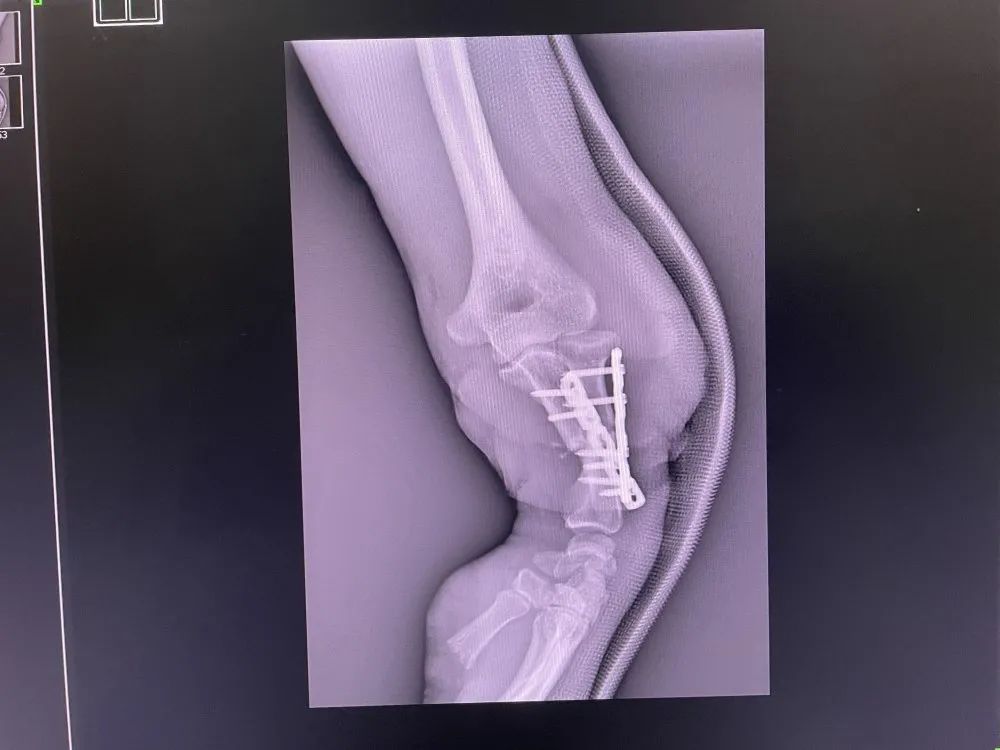

17:10,熊先生被送入手術室,在全麻下行左前臂離斷再植術+骨折內固定術+血管神經移植術+植皮術,醫生們熟練的清洗、消毒嚴重污染的創面和離斷肢體,熟練的清創壞死失活組織。由李龍付主任、蘇加向院長及褚偉鴻醫生組成的手術團隊,從容、迅速的用最短的時間完成手術最后的步驟:沖洗肢體后無菌敷料包扎、石膏托加強固定,十個小時,手術宣布結束。熊先生被送入ICU監護室,熊先生的家屬及工友們都松了一口氣

術后DR

1625448370477488.jpg

1625448370412535.jpg